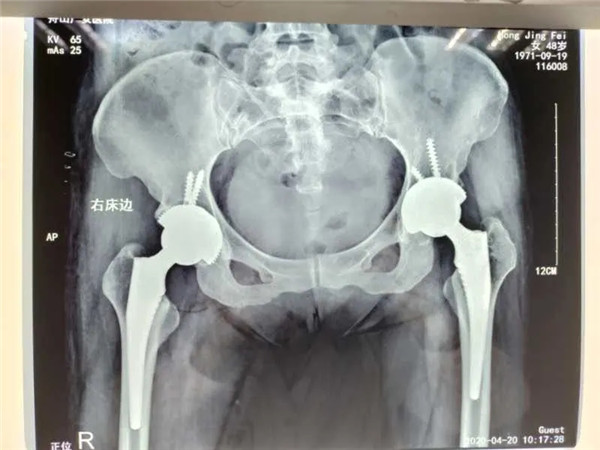

4月13日,危立軍副院長為洪女士實施了右側髖關節(jié)置換術,手術在關節(jié)鏡下完成,術后洪女士感覺良好。術后一周,洪女士便可以下地行走。目前,洪女士恢復良好,已經(jīng)出院回家休養(yǎng)。

雙側髖關節(jié)置換

值得一提的是,對于此次手術的人工關節(jié)材料,洪女士仍舊和三年前一樣,選擇了全陶瓷人工關節(jié)。